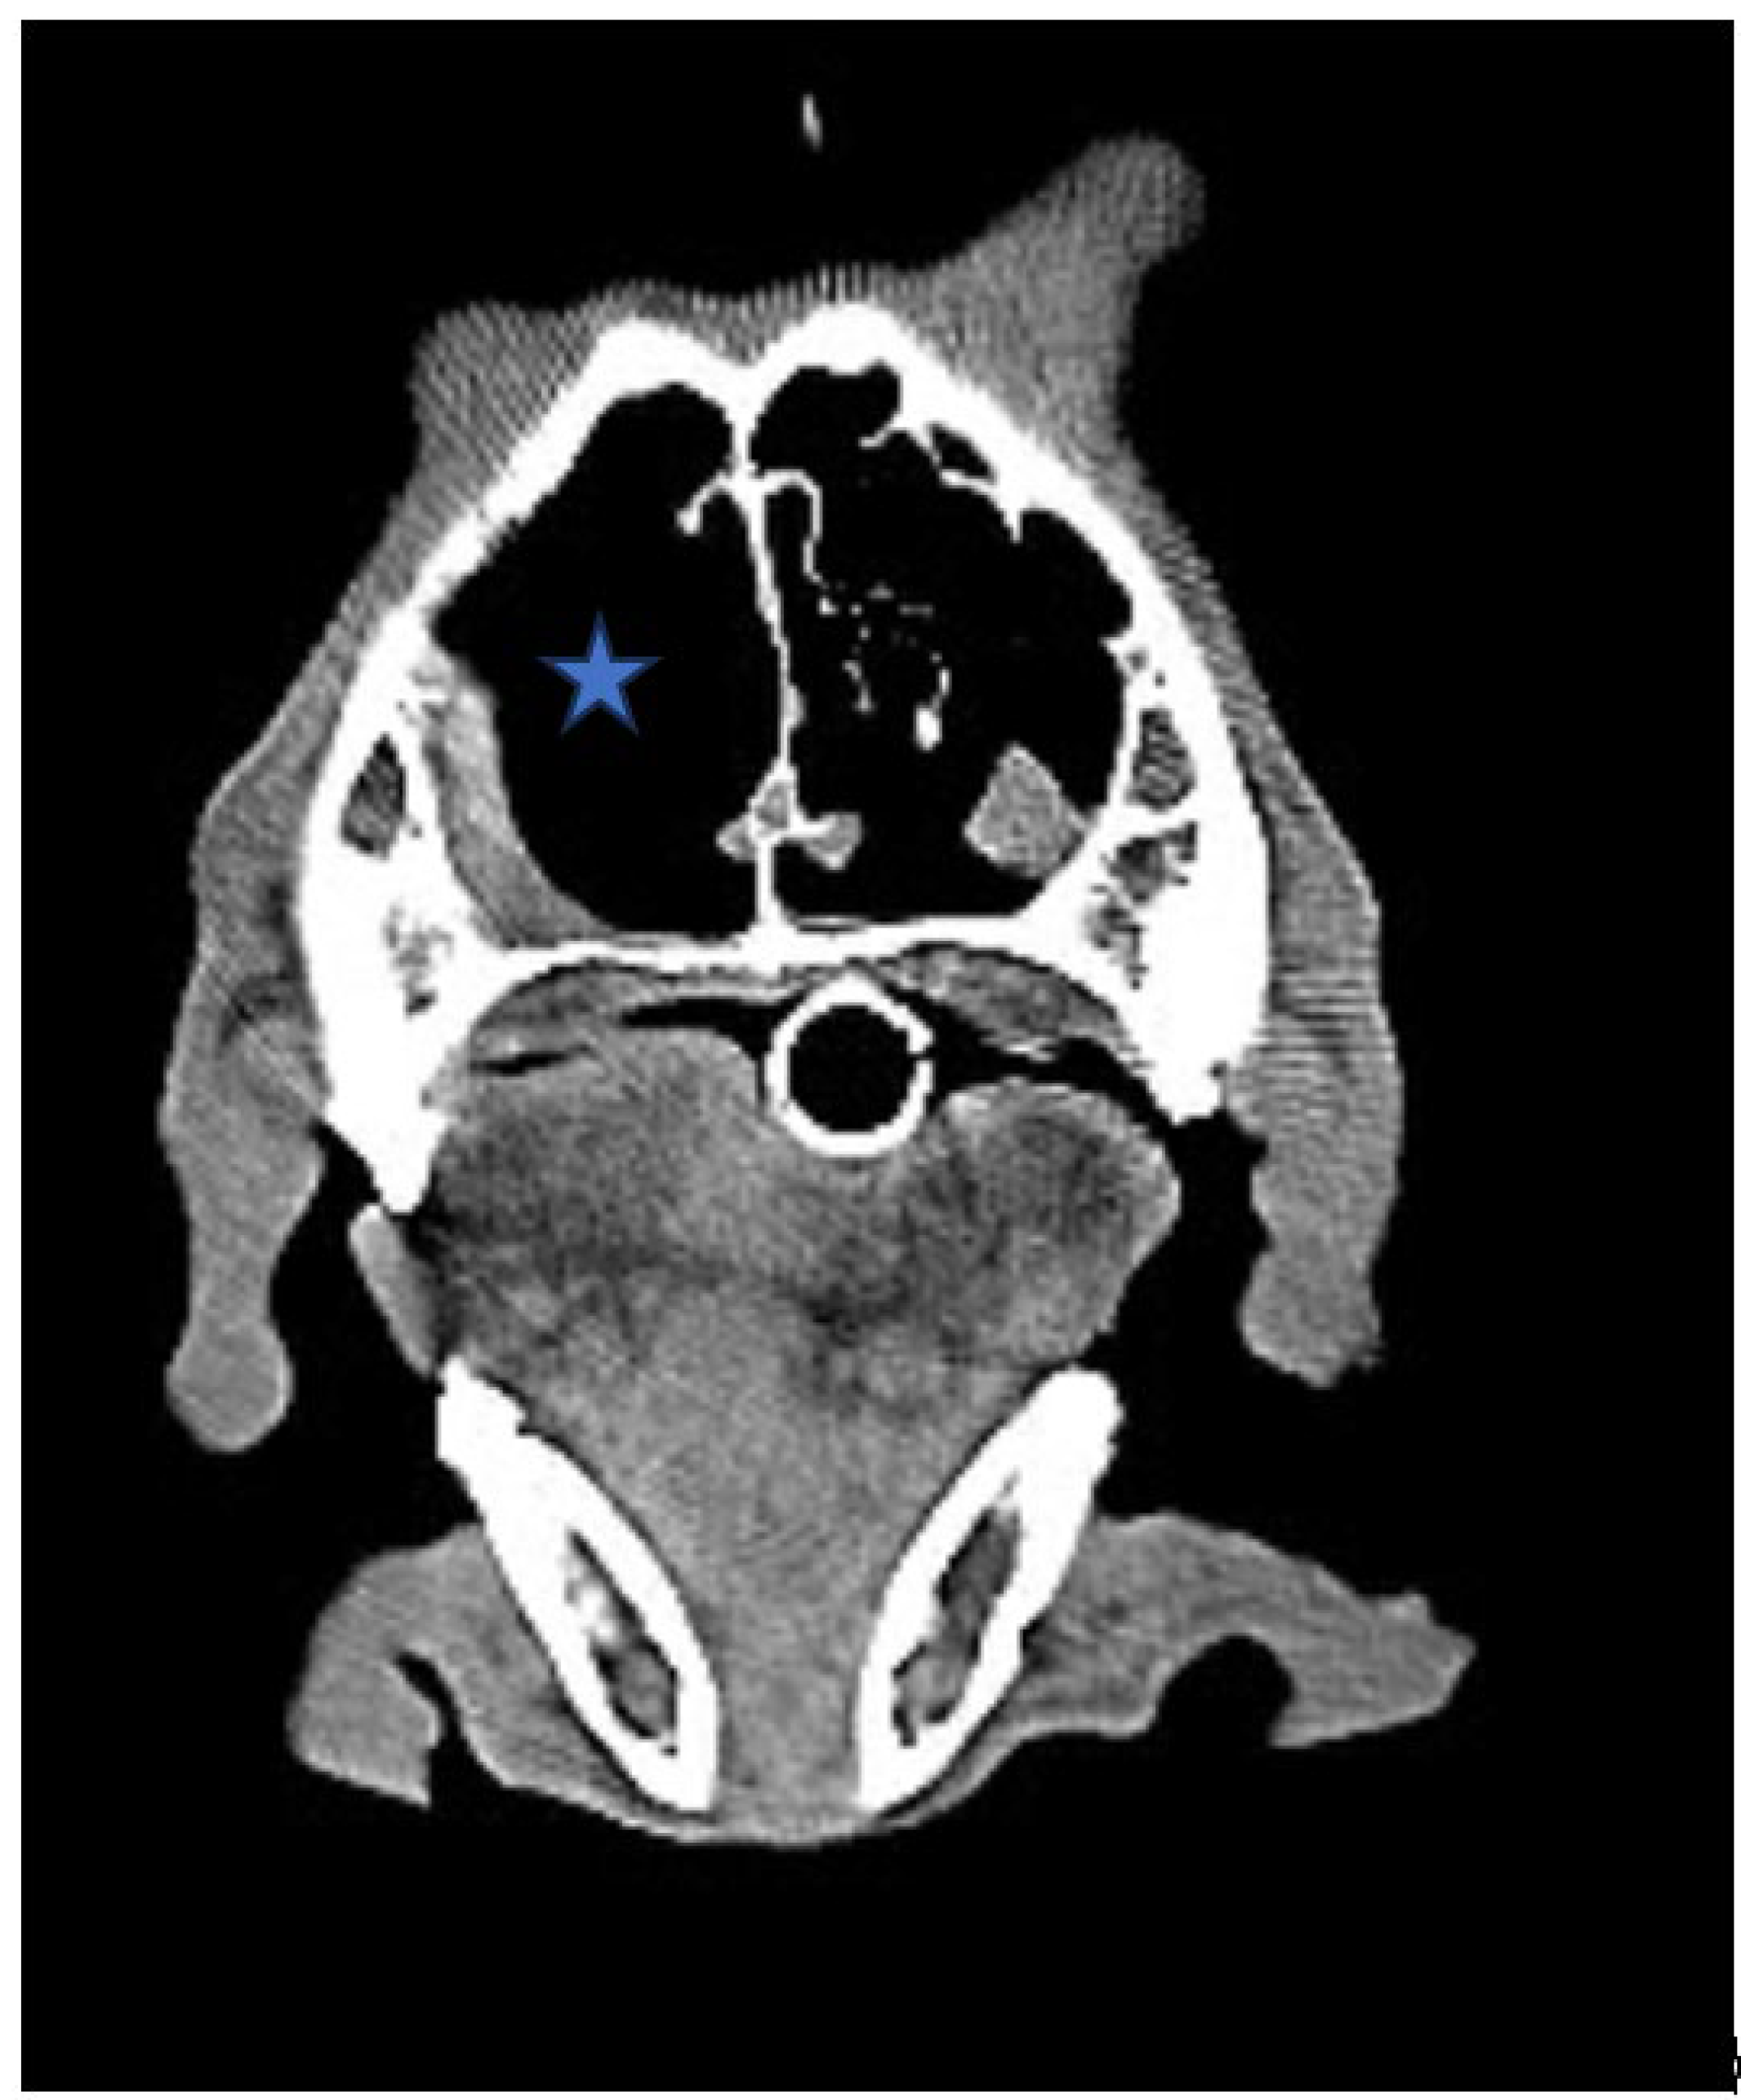

Figure 2. (A,B,C). Axial View of CT Scan of Skull

The size of the tumor decreased significantly after radiation/chemotherapy compared with before radiation/chemotherapy, after radiation, and before chemotherapy (Asteroid).